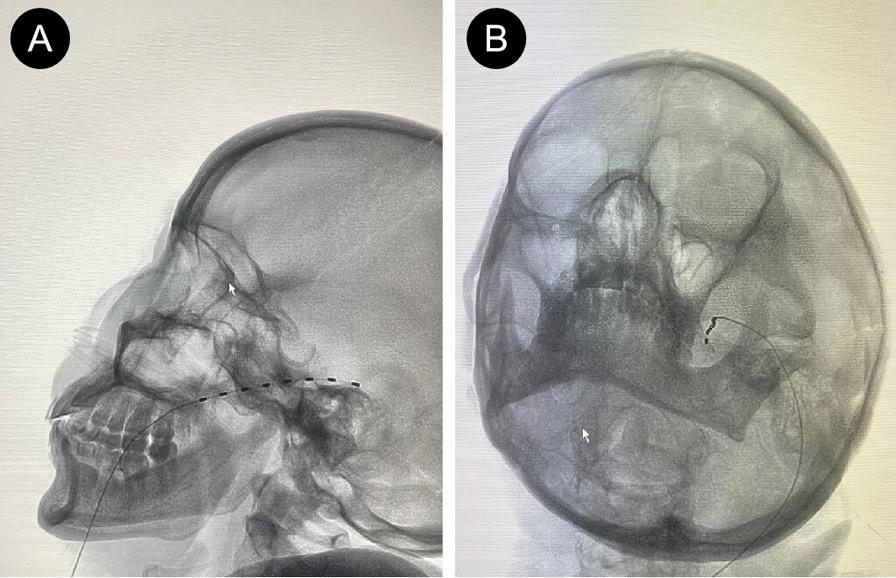

This study reports two cases of trigeminal herpes zoster that were refractory to pharmacological treatment and successfully alleviated using trigeminal ganglion electrical stimulation, which also effectively prevented postherpetic neuralgia. Both patients, a 62-year-old Chinese female and a 65-year-old Chinese male, presented with severe pain, itching, sensory disturbances, and extensive vesicular lesions on the left side of the face, involving the ophthalmic (V1) and maxillary (V2) branches. Despite receiving antiviral drugs, analgesics, and neurotrophic agents, their symptoms remained inadequately controlled, with pain scores ranging from 8 to 10. After undergoing trigeminal ganglion electrical stimulation, the pain score of both patients dropped to 2-3 on the first day post-treatment, with significant improvement in the herpes zoster blisters and pain. During follow-up, the pain continued to improve, with marked reduction in the pain and itching in the affected areas, and sleep quality also improved. At 1, 3, and 6 months of follow-up, neither patient had developed postherpetic neuralgia. These cases suggest that trigeminal ganglion electrical stimulation may be an effective method for treating refractory trigeminal herpes zoster and preventing postherpetic neuralgia, significantly improving herpes symptoms and alleviating pain.

本研究报告了两例药物治疗无效的三叉神经带状疱疹病例,通过三叉神经节电刺激成功缓解了症状,并且有效预防了疱疹后神经痛。两名患者,一名62岁的中国女性和一名65岁的中国男性,均表现为左侧面部严重疼痛、瘙痒、感觉障碍以及广泛的水疱性皮损,累及眼支(V1)和上颌支(V2)。尽管接受了抗病毒药物、镇痛药和神经营养药物治疗,他们的症状仍未得到充分控制,疼痛评分在8至10分之间。在接受三叉神经节电刺激后,两名患者在治疗后的第一天疼痛评分降至2 - 3分,带状疱疹水疱和疼痛均有显著改善。在随访期间,疼痛持续改善,受累区域的疼痛和瘙痒明显减轻,睡眠质量也有所提高。在随访的1个月、3个月和6个月时,两名患者均未发生疱疹后神经痛。这些病例表明,三叉神经节电刺激可能是治疗难治性三叉神经带状疱疹和预防疱疹后神经痛的有效方法,可显著改善疱疹症状并减轻疼痛。